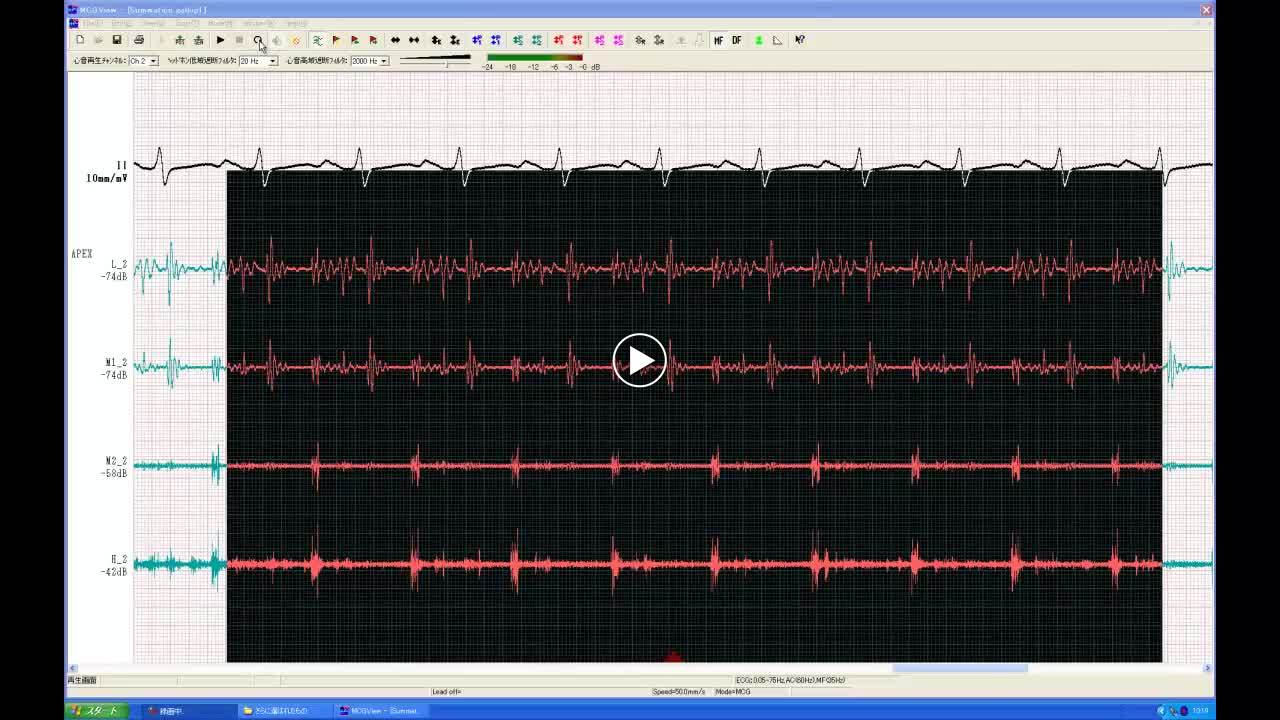

• 図5 典型的なギャロップ・リズム a

• 00:00:13